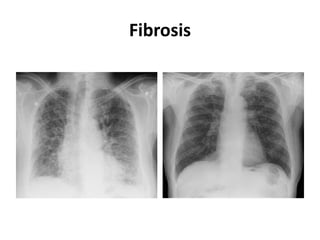

Fibrosis